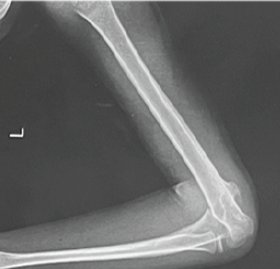

Harnessing 3D Printing Technology for Complex Acetabular Reconstruction in Revision Total Hip Arthroplasty: From Childhood Hip Trauma to Customized Modern Solutions